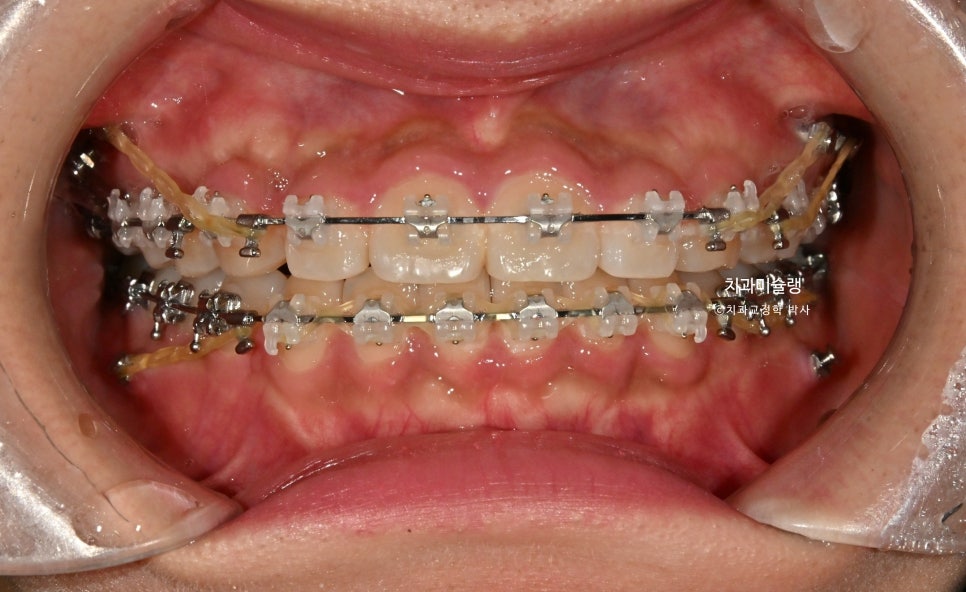

교정 치료 1년째 진행상황

클리피씨 교정 1년째 모습입니다.

상악엔 좌우 2개씩 총 4개, 하악에 좌우 1개씩 총 2개의 미니스크류를 심고 치료를 합니다.